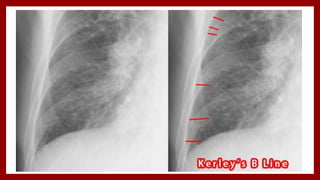

Chest X-Ray

• Cardiomegaly

• Cephalization of blood flow

• Kerley’s A lines [1- to 2-cm lines of

interstitial edema out from the hilum]

• Kerley’s B lines [short, thin, flattened

streaks of interstitial edema outlining

the subsegmental lymphatics that

extend from the pleural surface]

Chest X-Ray • Cardiomegaly •Cephalization of blood flow • Kerley’s A lines [1- to 2-cm lines of interstitial edema out from the hilum] • Kerley’s B lines [short, thin, flattened streaks of interstitial edema outlining the subsegmental lymphatics that extend from the pleural surface]